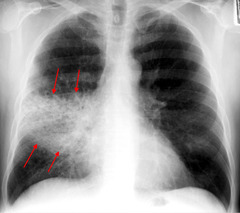

Cervical Carcinoma

Invasive carcinoma that arises from CIN-dysplasia Presentation: - middle aged woman - vaginal bleeding (esp post-coital) Risk factors: - high-risk HPV - smoking - immunodeficiency (cannot destroy virus) Complication: lateral invasion to ureters or anterior invasion to bladder --> hydronephrosis and post-renal failure --> death